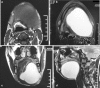

A case of chronic and slow growing massive lateral neck swelling is presented which gradually resulted in dysphagia to an extent that patient reported in emergency room. Clinical findings were indicative of a cystic swelling or a massive lipoma. Temporary decompression of the lesion was achieved by partially aspirating the contents of the cyst. Nature of aspirate and its microscopic and biochemical analysis excluded lipoma, vascular malformation and salivary phenomenon. The diagnosis tapered to developmental lateral neck cysts. Magnetic Resonance Imaging (MRI) revealed a massive cystic lesion in the left floor of mouth extending to the right lingual aspect of mandible and posteriorly to impinge on the medial wall of pharynx. A combined intraoral and extraoral approach was used to expose and excise the lesion in toto. Final histological diagnosis of the pathology was epidermoid cyst.